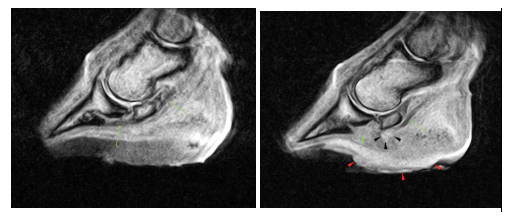

Repeat MRI a fortnight later (right image) revealed the draining tract to be larger (red arrowheads) compared to previous (left image) on the T2FSE frontal images. Additionally, a distinct loss of integrity of the lateral part of deep digital flexor tendon towards its insertion was visible (red arrows). This loss of integrity to the tendon was present from the level of the navicular bone to the insertion on the distal phalanx.

The T1 sagittal images with the previous scan to the left and the most recent to the right demonstrates the loss of integrity of the tendon distal to the navicular bone (green arrows). Fluid signal within the solar tissues and disruption of the architecture of the solar dermis and margin is demonstrated by the red arrowheads.